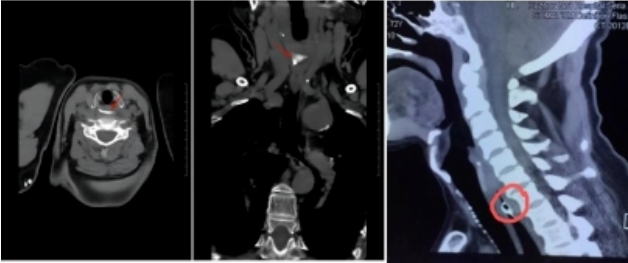

03.检查方法

目前临床的主要检查方法有:间接喉镜/纤维喉镜检查除外喉部卡顿;颈部X线片/颈胸部CT检查;食管镜或胃镜检查。